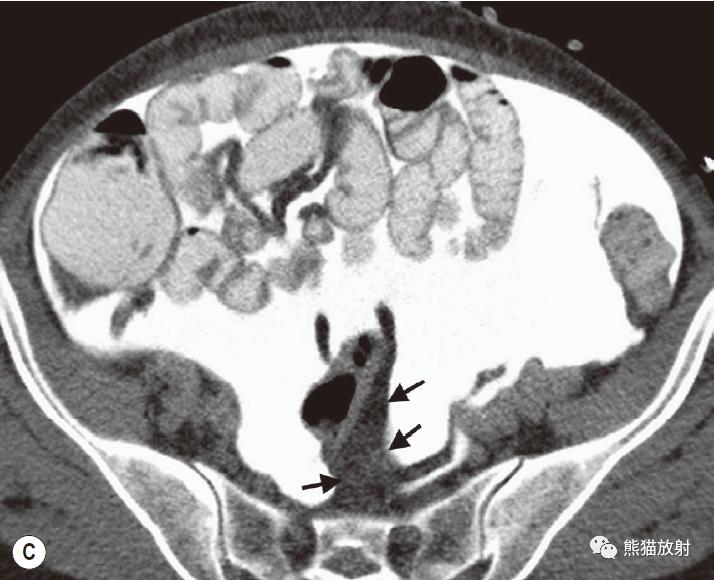

肠系膜疝。 扩张、充满液体的小肠襻丛位于前腹壁下的升结肠侧旁(箭),取代网膜脂肪。充盈的血管及邻近肠系膜模糊,反映了小肠绞窄性梗阻。